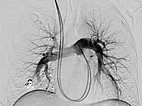

Upon evaluation of the underlying disease, contrast ultrasonography revealed a pulmonary right-to-left shunt, and computed tomography confirmed the finding of multiple pulmonary AVMs. Because of the size, there was an indication for embolization. Digital subtraction angiography demonstrates a pulmonary AVM in the upper lobe, already superselectively catheterized, with typical aneurysmally dilated arteriovenous shunt.